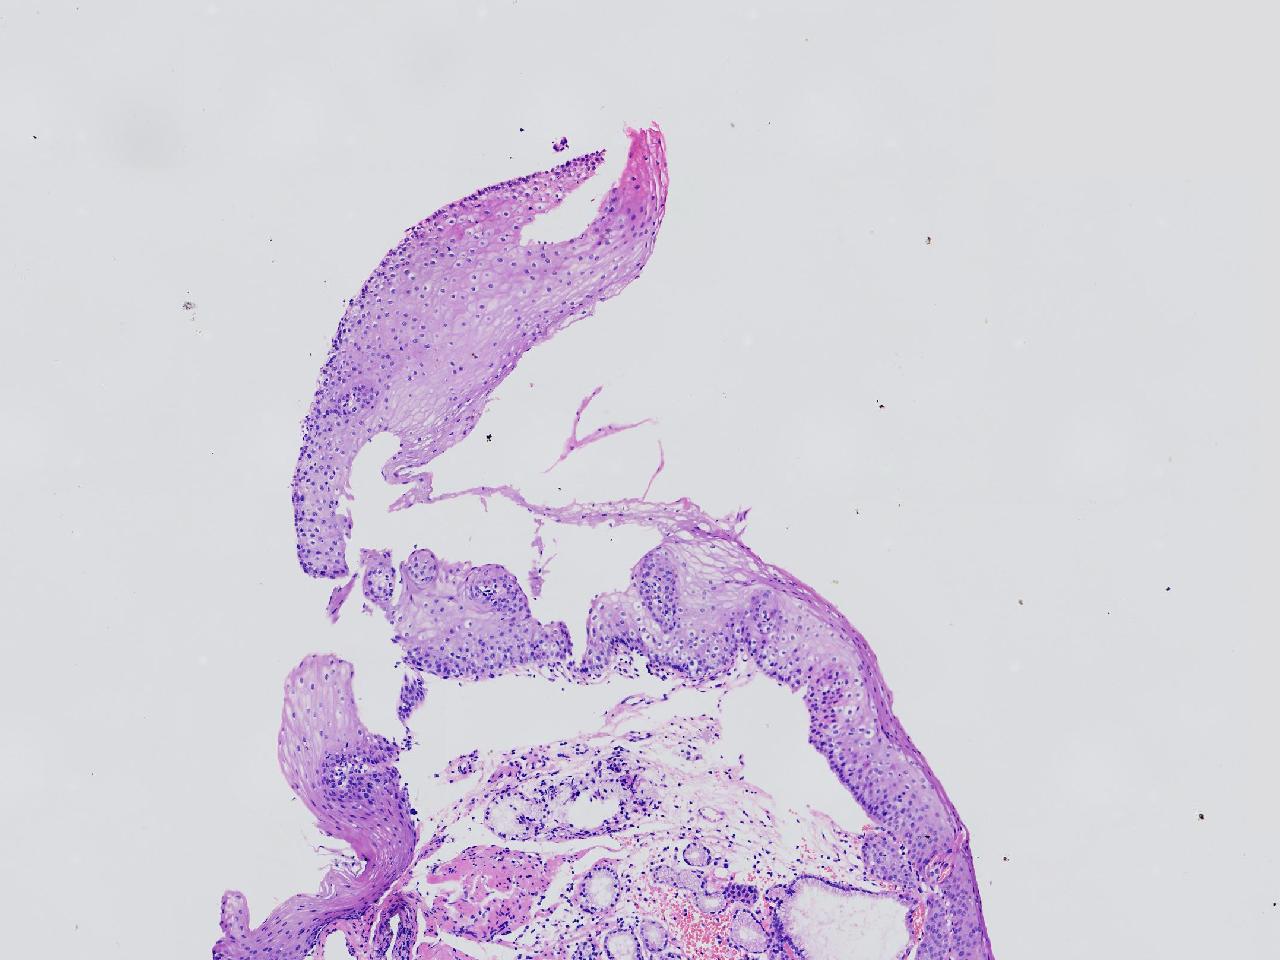

女,38岁,食管距门齿38cm处见一扁平隆起,表面粗糙,活检1块,质软,弹性可。

食管活检

灰白色不整形软组织1块,直径0.2厘米。

结合取材部位排除Barrett食管

粘膜慢性炎。

Barrett食管,粘膜慢性炎。